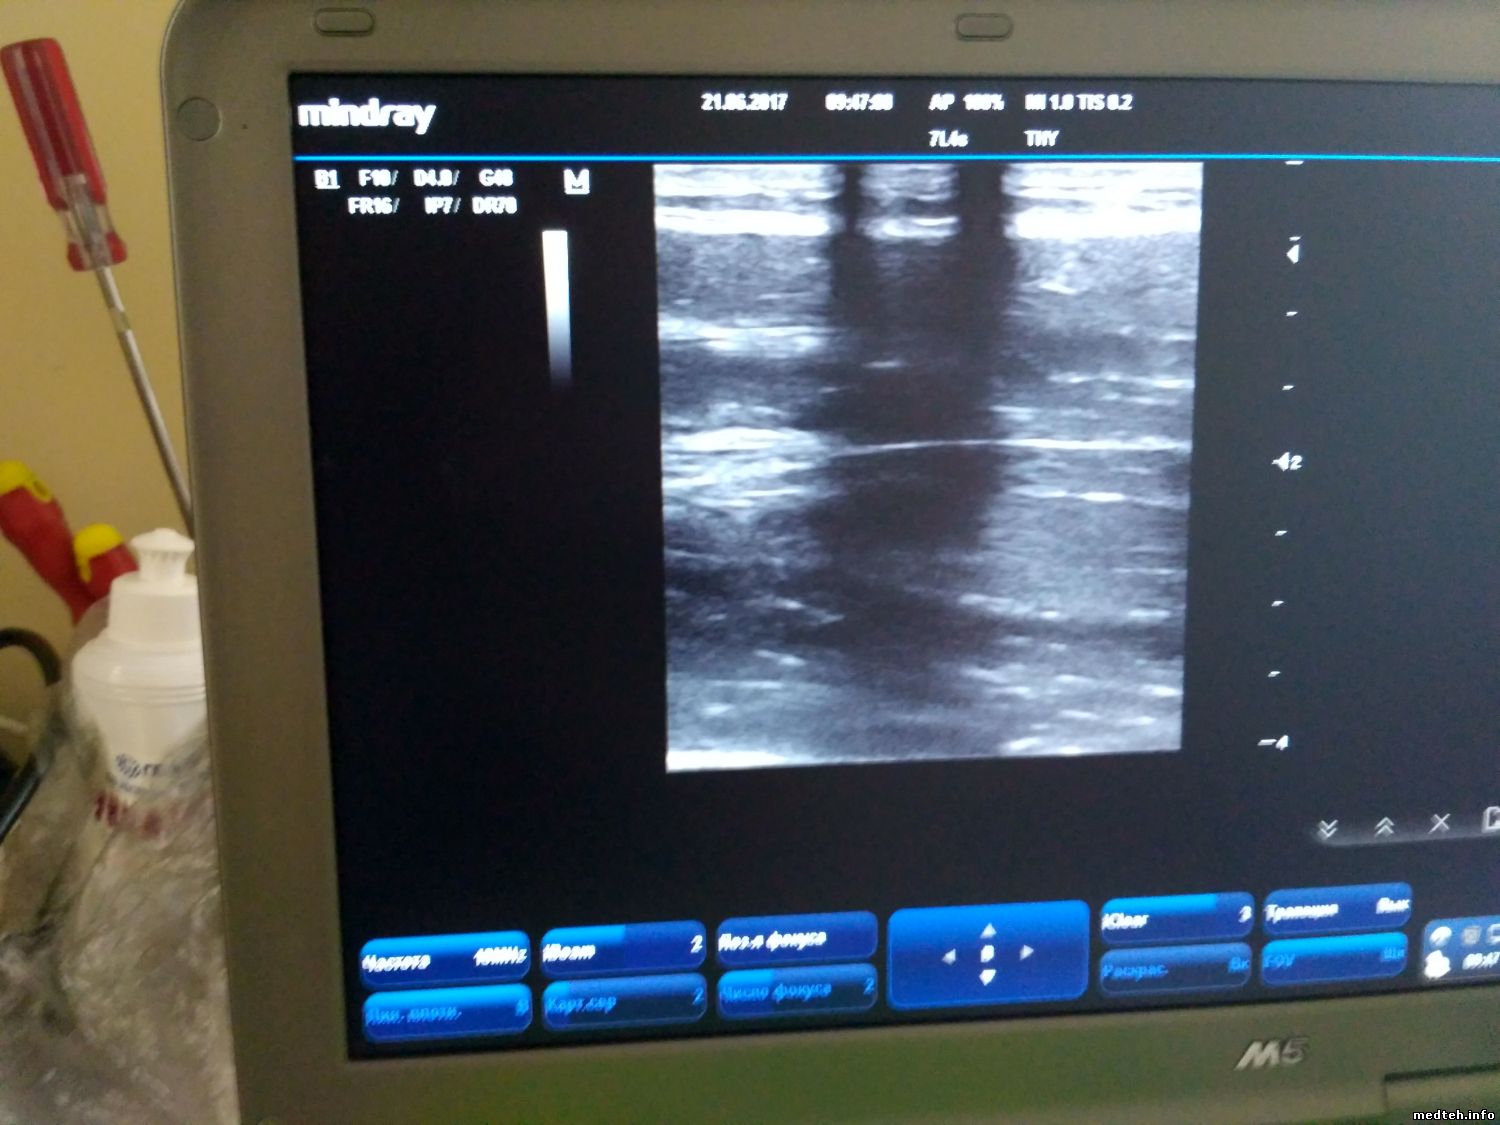

У Mindray M5 появились затемнения в виде двух полосок, которые срастаются в пятно по центру, при этом такая картина идентична на разных видах датчиков. Когда конвексный подключил к другому Миндрею М5, то там всё нормально.

Разъёмы смотрел, окиси нет, не гнутые.

Может есть калибровки или это железо глючит?

8885968.jpg (156.5 Kb)

Просто последний был конвексный. На первом фото полосы есть, на втором их нет (датчик один и тот же, аппараты разные).

1762746.jpg (148.7 Kb) · 7828479.jpg (158.8 Kb)